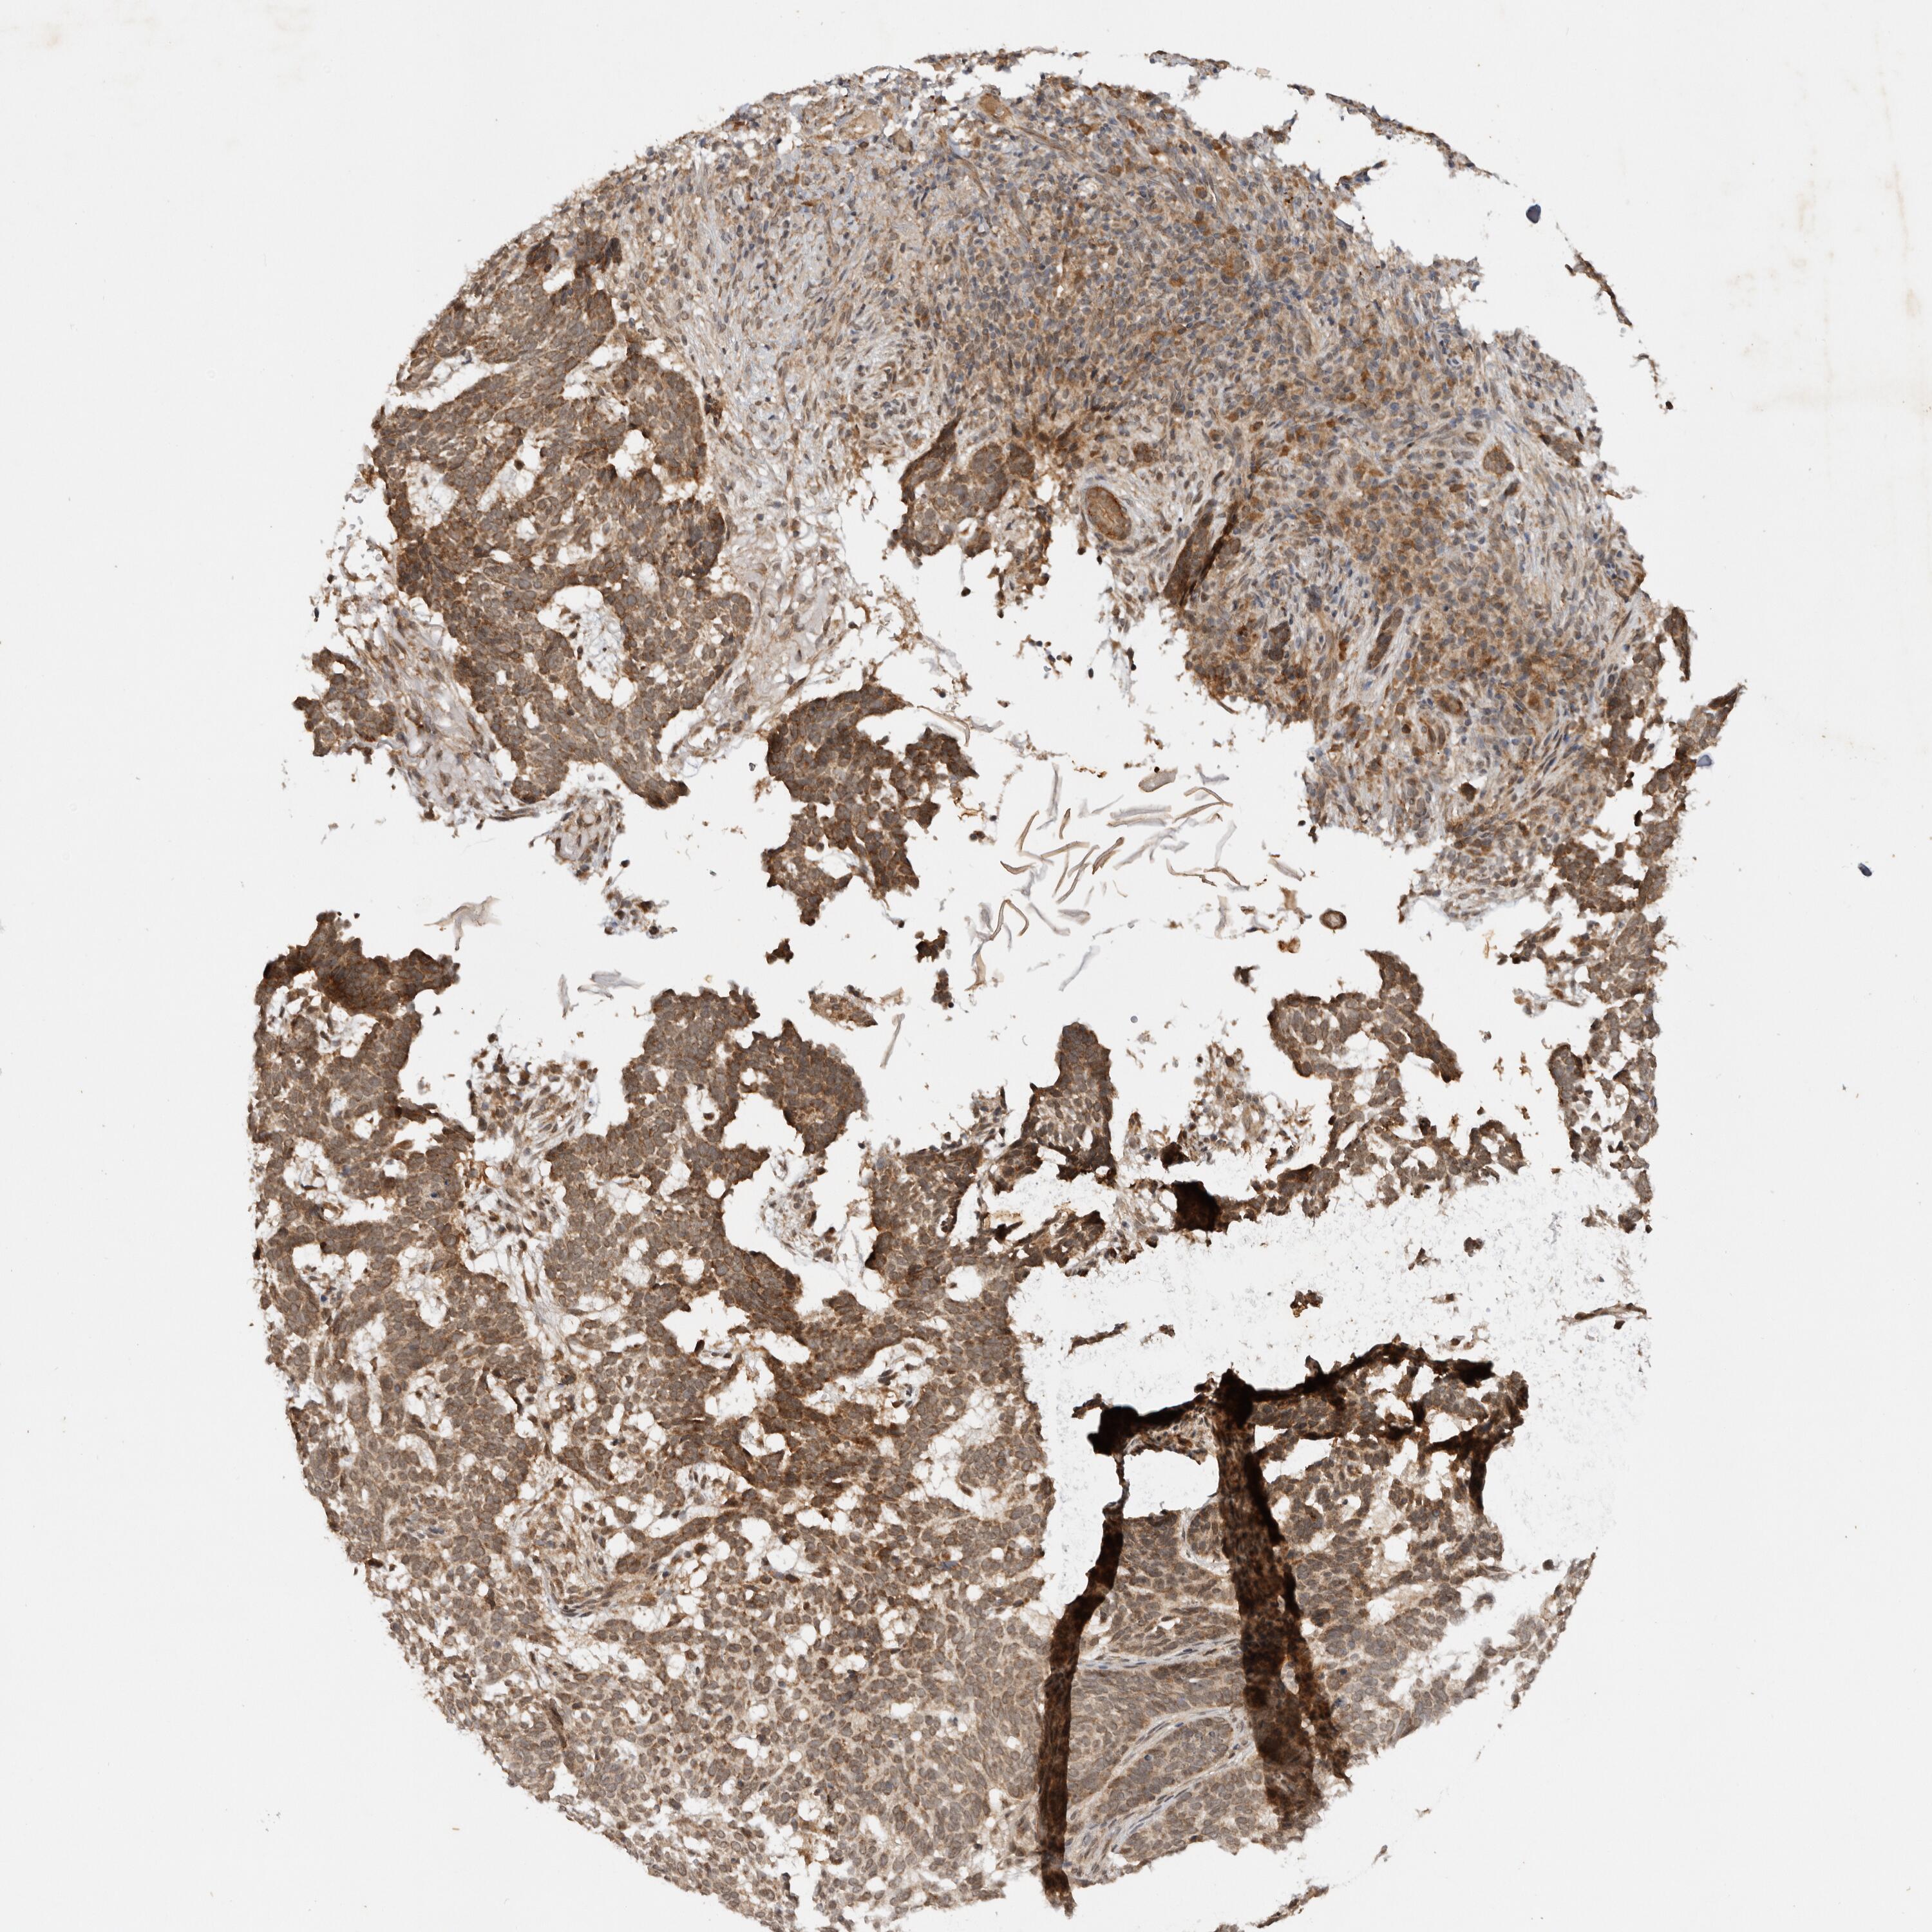

SKIN CANCER - Protein expressioni

A mouse-over function shows sample information and annotation data. Click on an image to view it in a full screen mode. Samples can be filtered based on level of antibody staining by selecting one or several of the following categories: high, medium, low and not detected. The assay and annotation is described here.

Antibody stainingi

Antibody staining in the annotated cell types in the current human tissue is reported as not detected, low, medium, or high, based on conventional immunohistochemistry profiling in selected tissues. This score is based on the combination of the staining intensity and fraction of stained cells.

Each image is clickable and will lead to virtual microscopy that enables deeper exploration of all samples and also displays staining intensity scores, fraction scores and subcellular localization as well as patient and tissue information for each sample.

Antibody HPA028626

Squamous cell carcinoma, NOS